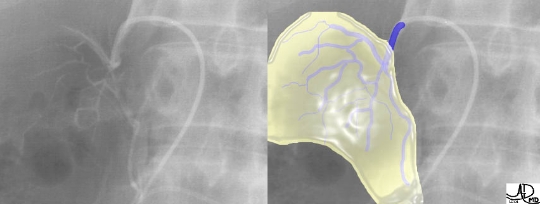

This image is an overlay and an enlarged version of the first image above. It shows the right catheter entering the short right adrenal vein, exiting from above the right gland, and entering the IVC. The left adrenal vein, which is longer, exits from below the left gland and enters into the left renal vein. The insert of the “duel” is a reminder of the short vein on the right and the long vein on the left. Courtesy of: Ashley Davidoff, M.D. |

This image is an overlay and an enlarged version of the second image from the initial series above. It shows the right catheter entering the shorter right adrenal vein, exiting from above the right gland, and entering the IVC. The yellow overlay is an approximation of the right adrenal gland. Courtesy of: Ashley Davidoff, M.D. |